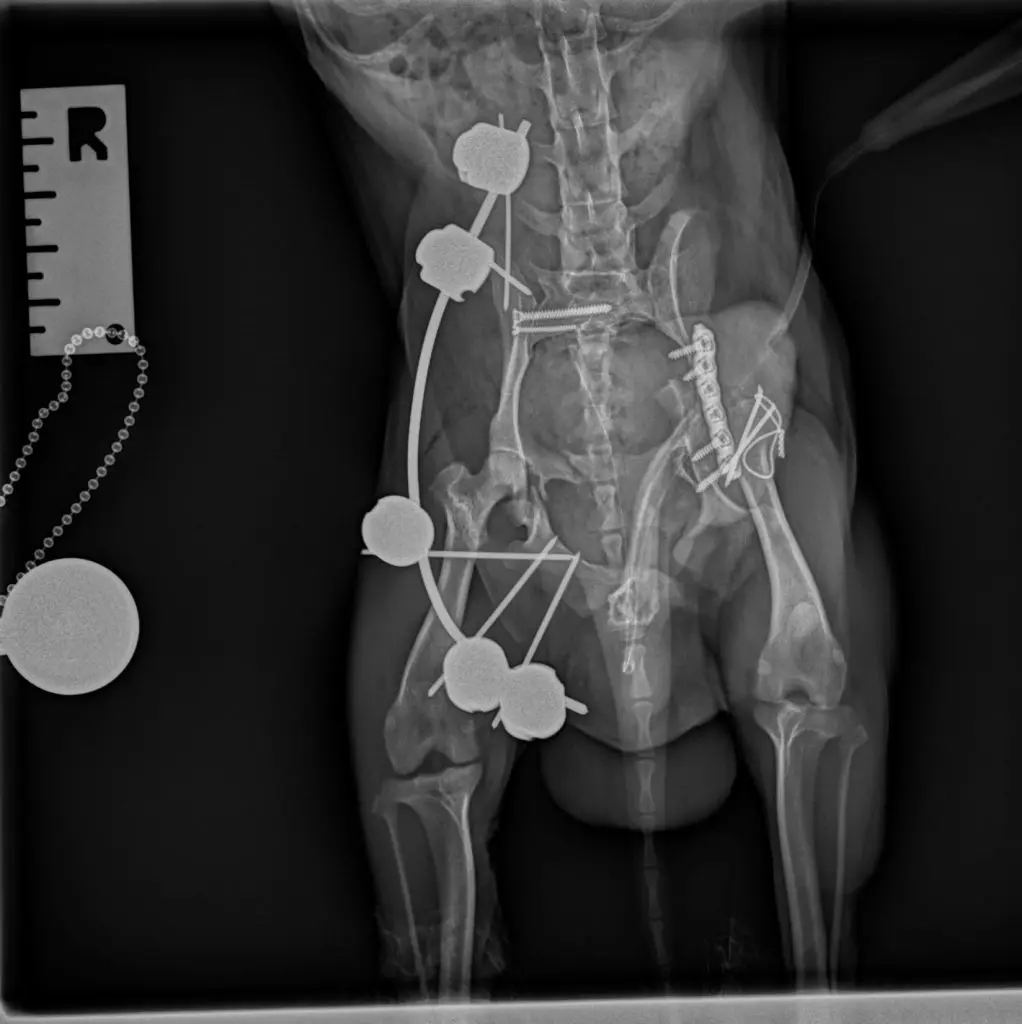

Para obtener un diagnóstico definido, procedimos a realizar un protocolo diagnóstico completo, que incluyó un estudio radiológico y tomográfico de la pelvis. Gracias a las imágenes pudimos confirmar el diagnóstico, una fractura múltiple de pelvis con luxación sacroiliaca derecha, y luxación coxofemoral izquierda a consecuencia de una fractura conminuta del acetábulo.

Para poder definir con mas precisión todos los daños y establecer el mejor plan quirúrgico realizamos una tomografía computarizada (TAC) de la pelvis.

La estabilización quirúrgica de la pelvis no resultó sencilla. En primer lugar se realizó un abordaje lateral al ilion y acetábulo izquierdo, a través de una osteotomía de trocánter mayor. Al comprobar la imposibilidad de reducción de los fragmentos que comprometían el acetábulo, se tomó la determinación de realizar una exéresis de la cabeza y cuello femoral. A continuación se estabilizó la fractura de la hemipelvis izquierda mediante una placa de bloqueo y titanio de 1´5 mm. La osteotomía del trocánter mayor se redujo y estabilizó por su lado con una banda de tensión.

En segundo lugar se realizó un abordaje dorsal a la articulación sacroiliaca derecha, que se encontraba luxada. Se redujo y estabilizó con dos tornillos para garantizar la fijación adecuada.

Por último, una vez cerrados los abordajes, se decide colocar un fijador externo en la hemipelvis derecha para dar un soporte adicional a la musculatura, especialmente la relacionada con el isquion.